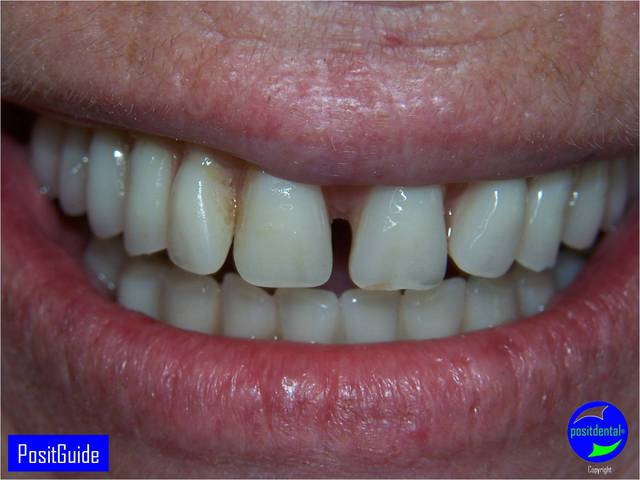

Mise en Charge Immédiate Post Extractionnelle , MCIPE partie chirurgicale de A à Z

Je trouve ces cas très bien réalisés, rapide et impressionnants.

Cependant, qu'en est-il de la stabilité sur le long terme dans dans des contextes paro aussi sévère.